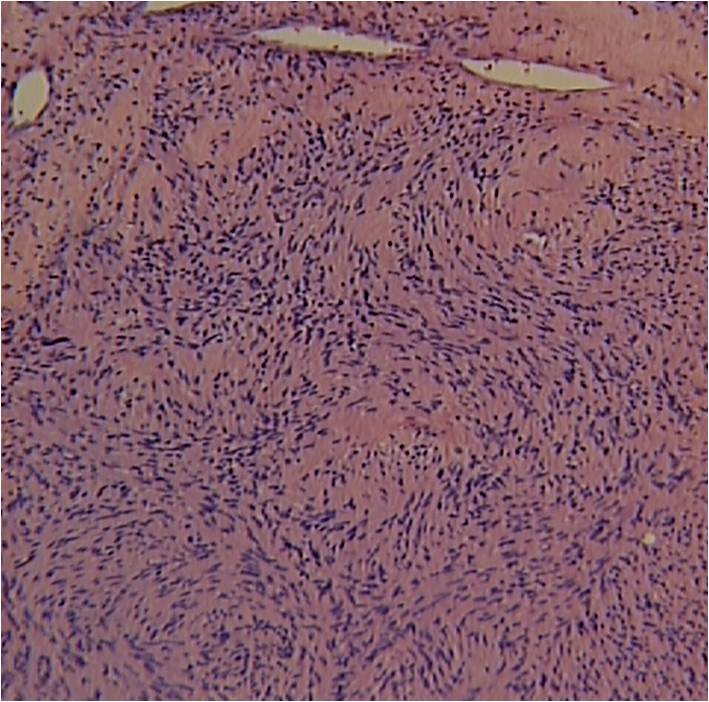

Microscopic Pathology

• Usually uninodular masses

• Surrounded by fibrous capsules consisting of epineurium and residual nerve fibers

• Distinct Pattern of alternating Antoni A and B areas

o Antoni A Area: Cellular area arranged in short bundles or interlacing fascicles

Spindle cells with wavy appearing nuclei. (Fig. 5 & 6)

o Antoni B Area: Less cellular and more myxoid (Fig. 7)

• Ancient schwannomas: a type of schwannoma that is typically larger and demonstrates cyst formation, calcification, hemorrhage, fibrosis. Ancient schwannomas can be mistaken for malignant peripheral nerve sheath tumors

• Mitotic activity is rare.

• S-100 positive staining; Vimentin positive

Fig. 5-7 Microscopic Pathology demonstrates 2 different patterns; Antoni A area with spindled hypercellular distribution with wavy appearing nuclei (Fig 5 & 6A) that palisades, known as Verocay Bodies (Fig 6B). Antoni B area is less cellular and more myxoid (Fig 7) than the Antoni A area. Mitotic activity is not visible.